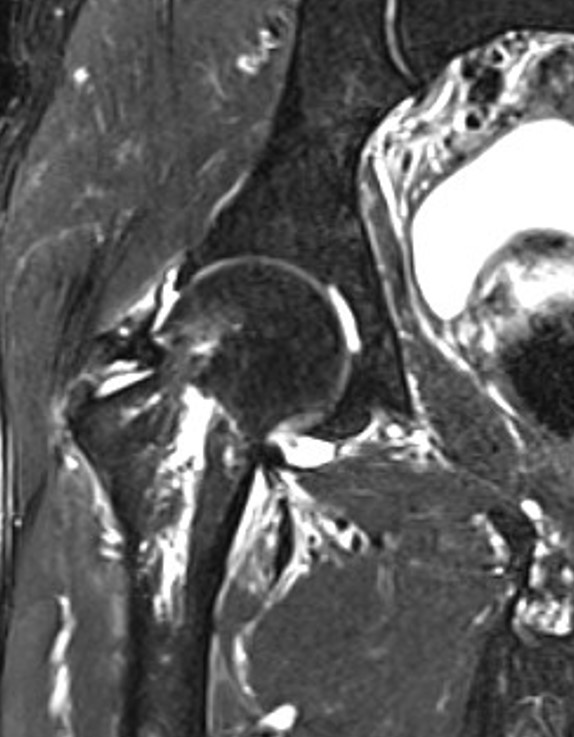

RevolutionApexElite_Uonuma209.jpg

図8 STIR